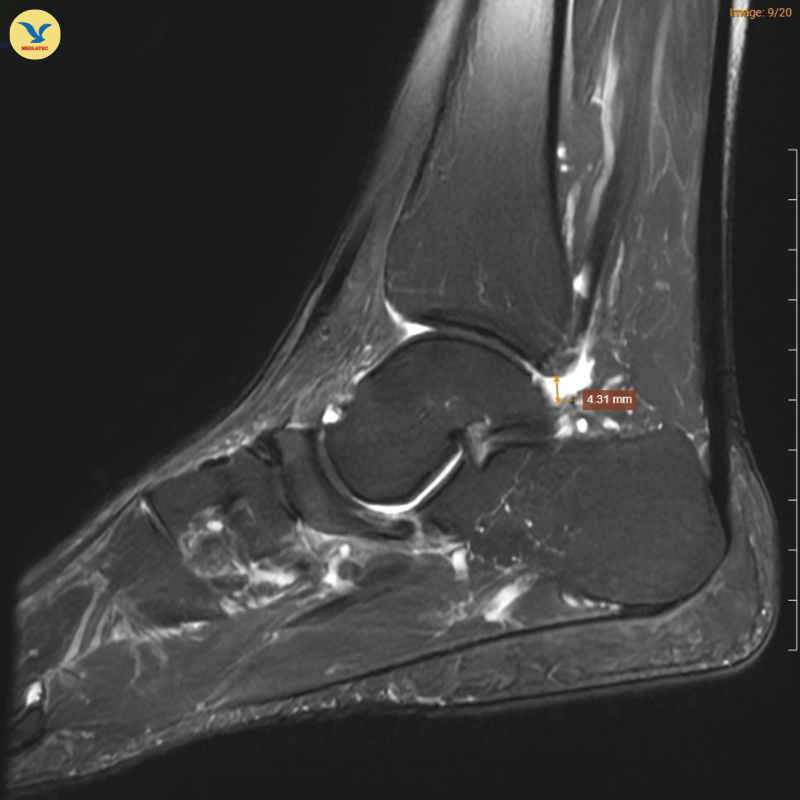

Hình ảnh chụp MRI cho thấy những dấu hiệu đặc trưng của Hội chứng Mueller-Weiss ở chân phải

Tại MEDLATEC, bác sĩ đã chỉ định chụp Cộng hưởng từ (MRI) để tìm kiếm những tổn thương sâu trong cấu trúc xương. Trên lát cắt Sagittal T1W, hình ảnh cho thấy xương ghe bị xẹp và biến dạng điển hình hình dấu phẩy, kèm theo tình trạng đặc xương dưới sụn. Trên chuỗi xung T2W FS, ghi nhận tình trạng phù tủy xương ghe rõ rệt.